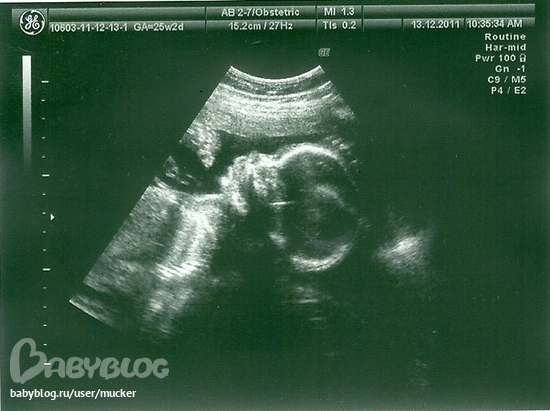

Муж вместе с врачом всё подробно посмотрел, а мне экран не стали поворачивать. Зато распечатали портрет нашей малышки) да, нам сказали, что у нас однозначно девочка) всё-таки я облажалась со своими прогнозами мальчика, а мама моя выиграла)

По срокам поставили 23 недели и 6 дней. по роддомовским меркам у меня ровно 23 недели. ну да ладно) малышка сидит на попе, хотя было бы неплохо, чтобы уже была головой вниз, как сказала узистка. но мне так спокойней, малышка точно сейчас никуда не собирается...а то я ведь родилась в 24 недели. и время перевернуться у неё есть.